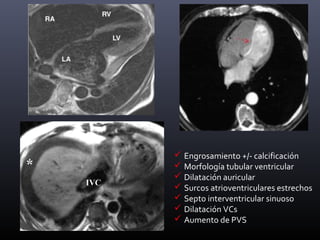

 Engrosamiento +/- calcificación

 Morfología tubular ventricular

 Dilatación auricular

 Surcos atrioventriculares estrechos

 Septo interventricular sinuoso

 Dilatación VCs

 Aumento de PVS